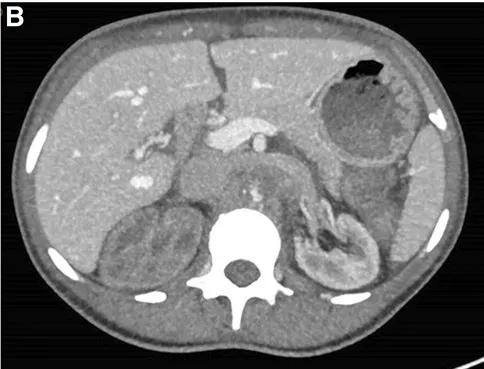

Se realizó una ecografía renal con Doppler que mostró ecogenicidad y tamaño renal normales, pero signos de oclusión aórtica en la emergencia de la arteria mesentérica superior, lo que fue confirmado por una tomografía computarizada con contraste (Figura 1).

La TC también reveló una importante circulación colateral en la pared abdominal, lo que permitía un suministro sanguíneo suficiente a las extremidades inferiores. Solo el riñón izquierdo mostró captación residual de contraste (Figura 1), lo que sugería un riñón derecho isquémico.

TC con contraste (reconstrucción 3D) mostrando oclusión aguda de la aorta justo superior a la arteria mesentérica. (A) Oclusión aórtica justo superior a la arteria mesentérica (marcada con un ⊗) junto con vasos colaterales en la pared abdominal (B) Riñón izquierdo con realce de contraste y riñón derecho sin realce, lo que sugiere falta de perfusión renal.